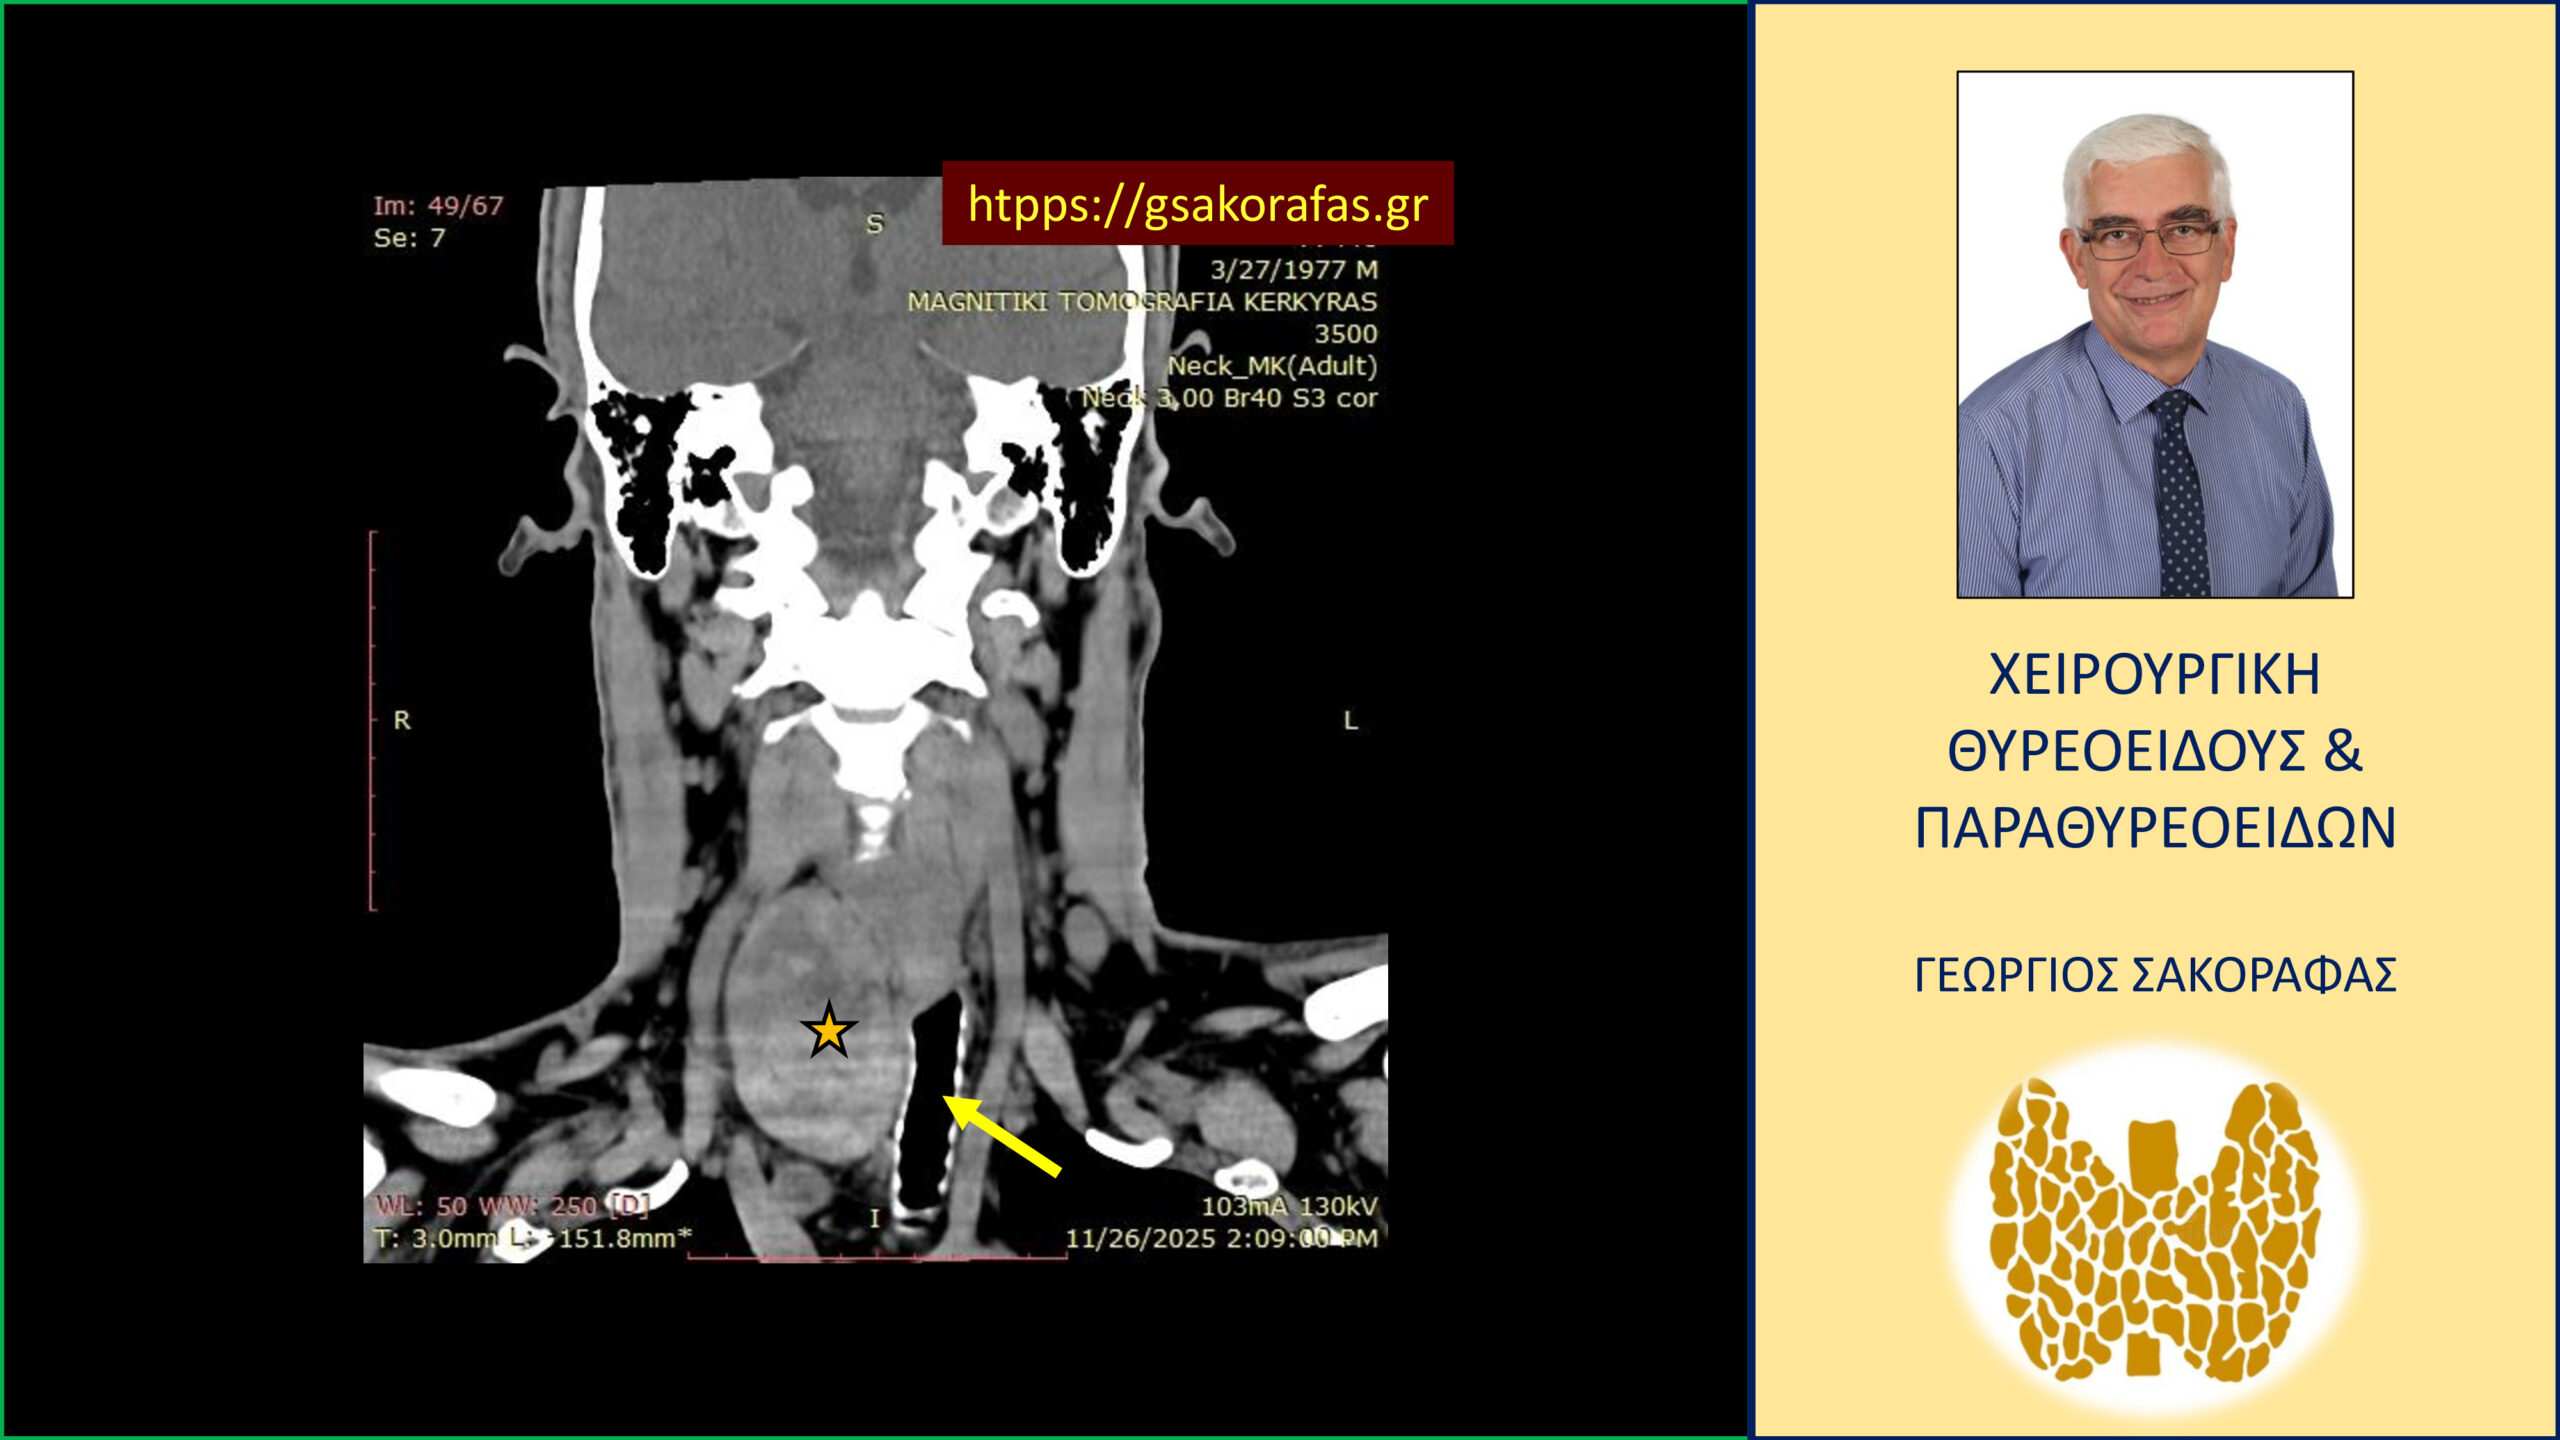

Για την αξιολόγηση του βαθμού κατάδυσης του δεξιού λοβού στο μεσοθωράκιο ο ασθενής υποβλήθηκε σε αξονική τομογραφία, στην οποία απεικονίζεται σημαντικού βαθμού αύξηση των διαστάσεων του θυρεοειδούς και κυρίως του δεξιού λοβού (δεξιός λοβός 74 x 57 x 50 mm, αριστερός λοβός 63 x 33 x 21 mm). Ο δεξιός λοβός καταδύεται στο μεσοθωράκιο. Απωθεί την τραχεία προς τα αριστερά.

Καταδυόμενη βρογχοκήλη με πιεστικά φαινόμενα από την τραχεία – με αφορμή ασθενή μας (εικόνες). Ο διογκωμένος καταδυόμενος δεξιός λοβός του θυρεοειδούς (κίτρινος αστερίσκος) απωθεί προς τα αριστερά την τραχεία (κίτρινο βέλος). Εικόνα σε κατά μέτωπον διατομή.